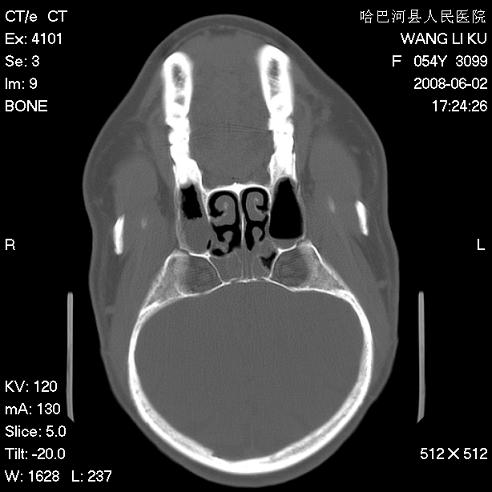

标题: CT13803:反复性鼻塞、流涕一年余 [打印本页]

标题: CT13803:反复性鼻塞、流涕一年余

副鼻窦炎,右上额窦积脓。左眼肌锥内见致密影,视神經受压

1.全组副鼻窦炎2.双侧上颌窦积液

1)全副鼻窦炎(左侧上颌窦黏膜下囊肿或息肉)。2)左眼眶肌锥内不规则小结节状软组织密度影;考虑为小血管瘤可能。建议行ct增强扫描检查。

全组副鼻窦炎,左侧肌锥内不规则形软组织肿块影,与眼外肌密度相当,左侧视神经受压,肿块与视神经及眼外肌分界清晰,眼外肌无增粗,眶壁无破坏,球后脂肪间隙不模糊,考虑良性改变,小血管瘤或神经源性肿瘤可能,建议增强扫描。

谢谢,增强扫描做了,眶内病灶与海绵窦同步明显强化,血管瘤